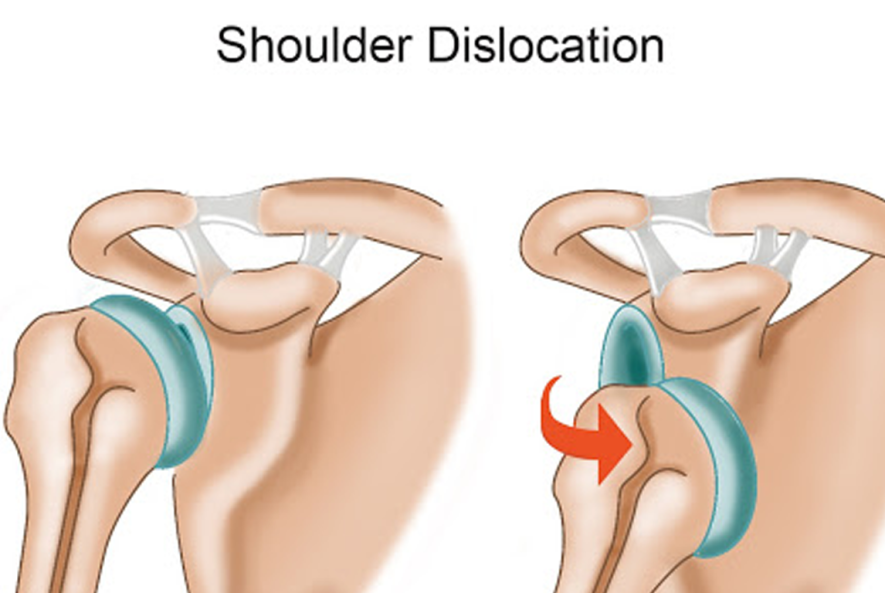

در رفتگی کتف چیست؟

دررفتگی کتف یکی از آسیبهای شایع مفصل شانه است که معمولاً در اثر ضربه شدید یا حرکت ناگهانی بازو رخ میدهد. در این حالت، سر استخوان بازو از جایگاه طبیعی خود در حفره گلنوئید خارج میشود و باعث درد شدید، تورم، و ناتوانی در حرکت دادن شانه میگردد. این آسیب میتواند به اعصاب و رباطهای اطراف نیز صدمه بزند و در صورت عدم درمان مناسب، احتمال دررفتگیهای مکرر را افزایش دهد. درمان شامل جا انداختن مفصل توسط پزشک، بیحرکتسازی شانه، و انجام فیزیوتراپی برای بازیابی عملکرد طبیعی است. پیشگیری از این آسیب با تقویت عضلات شانه و پرهیز از حرکات پرخطر امکانپذیر است.

دررفتگی کتف معمولاً در اثر وارد شدن نیروی شدید یا حرکت ناگهانی به مفصل شانه رخ میدهد که باعث خارج شدن سر استخوان بازو از حفره گلنوئید میشود. این آسیب اغلب در ورزشهای تماسی، سقوط روی دست باز، یا تصادفهای رانندگی دیده میشود. همچنین ضعف عضلات اطراف شانه، شل بودن رباطها، یا سابقه دررفتگی قبلی میتواند خطر بروز مجدد آن را افزایش دهد. مفصل شانه به دلیل دامنه حرکتی بالا، نسبت به سایر مفاصل بدن بیشتر مستعد دررفتگی است و نیازمند مراقبت و تقویت عضلات برای پیشگیری از آسیبهای احتمالی است.